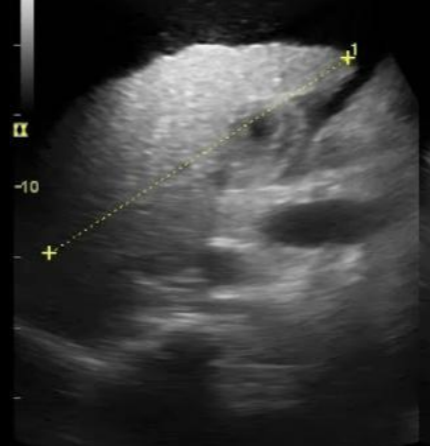

Q

A

probable hígado graso

10

Muy blanco y con textura gruesa en margenes

Cirrosis